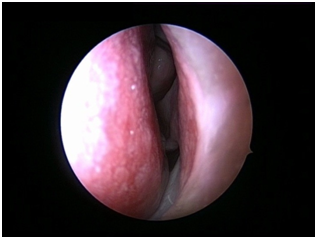

Nasal Endoscopy is done to assess the septal deviation and spurs (Figure 1) ( Figure 2). Septal infiltration is carried out with a solution of 2% Xylocaine with 1: 100,000 adrenaline in the sub-mucosal plane. It is given with a single prick at the inferior most part of the nasal septum at the junction of the septum with the floor of the nasal cavity anterior to the mucocutaneous junction. The infiltration is given at the same point on both the sides (Figure 3). The incision is always given on the deviated side. It is given anterior to the mucocutaneous junction because the skin present at that place is thick and chance of a tear of the flap is less (Figure 4). The mucoperichondrial flap is raised on the deviated side with a Freer’s elevator strictly under vision. The flap is not to be raised beyond the deviated part because the part of the septum posterior to the deviation is not under direct vision (Figure 5) (Figure 6). The caudal end of the septum is then palpated and an incision is given on the cartilage 1cm behind the columella. This 1cm of the cartilage is saved to prevent post operative tip deformities (Figure 7). The cartilage is sliced and the opposite side is entered, the mucoperichondrial flap of the opposite side is then elevated with a Freer’s elevator. A cut is given in the septal cartilage as high as possible. A septal window is created and a Ballenger’s swivel knife is taken and lodged in the place where the cartilage was cut. Creation of a septal window thus increases the area of exposure (Figure 8) (Figure 9). The flap on the non-deviated side is elevated till the bony-cartilaginous junction.

Figure 2 Spur present towards left side.